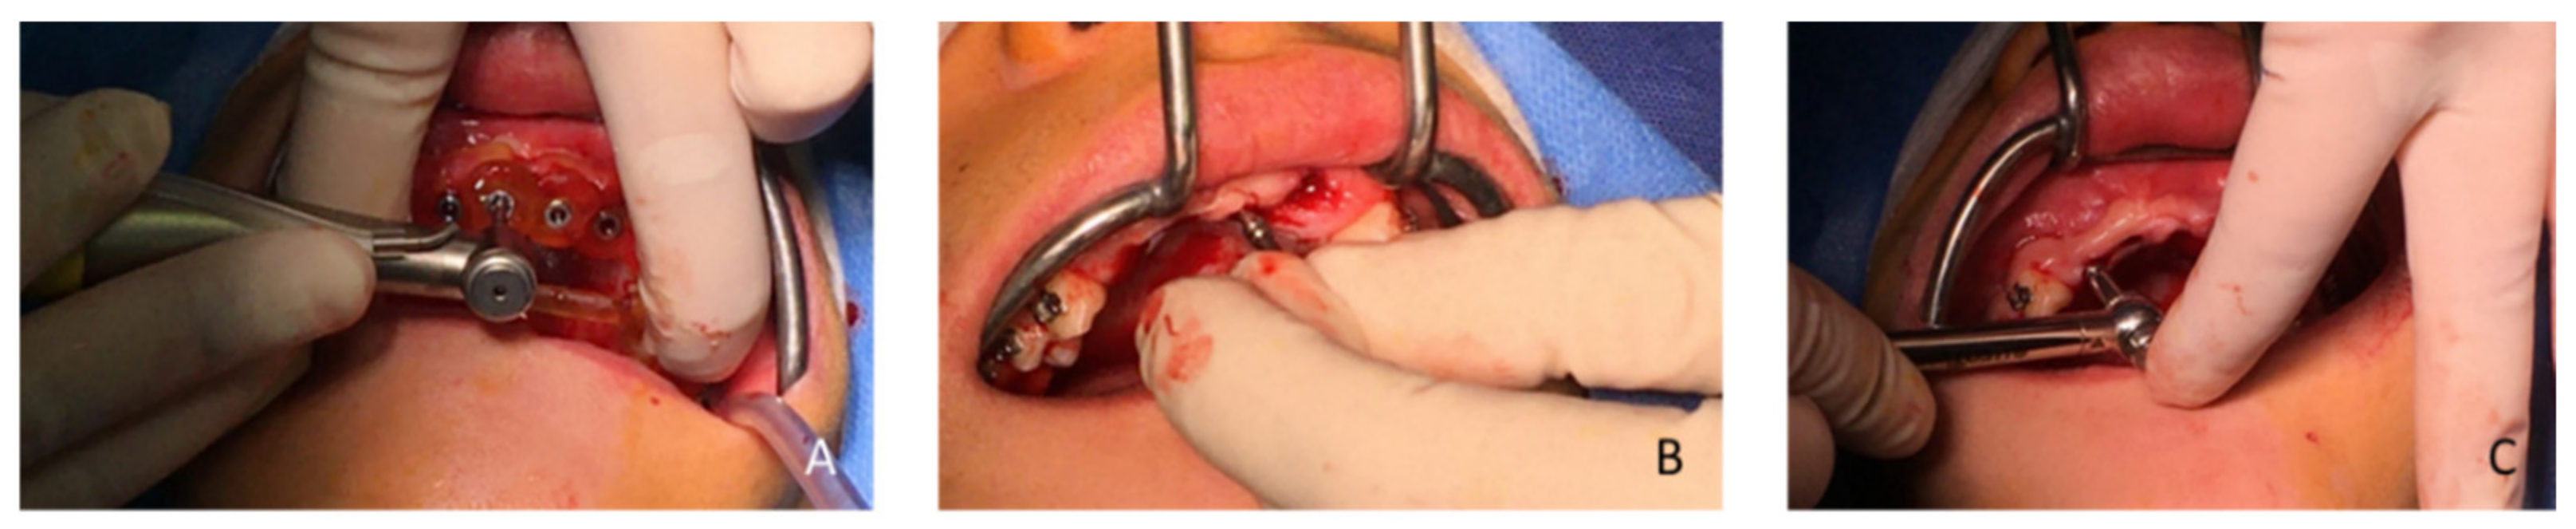

| May 2018 | Buccal and palatal flap of upper right anterior teeth without discharge/curettage of the granulation tissue/endodontic (lesion was of interest to the pulp)/restoration with a composite resin under dam/endodontics treatment with sodium hypochlorite irrigation and obturation at BioRoot™ and calibrated cone | Buccal flap without discharge from upper left anterior teeth/curettage of the granulation tissue/restoration with a composite resin under dam | ||

| Figure 6 and Figure 7 | ||||